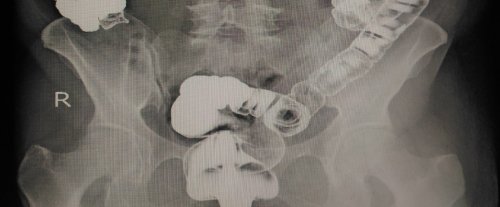

Cirujano Coloproctólogo

Cirugía especializada del colon, recto y ano

Cáncer de colon

Evaluación, diagnóstico y tratamiento quirúrgico.

Cáncer de recto

Manejo médico-quirúrgico

y especializado.

Enfermedad diverticular

Manejo clínico y quirúrgico

del colon.

Patologías del colon y recto

Atención médica integral

especializada.